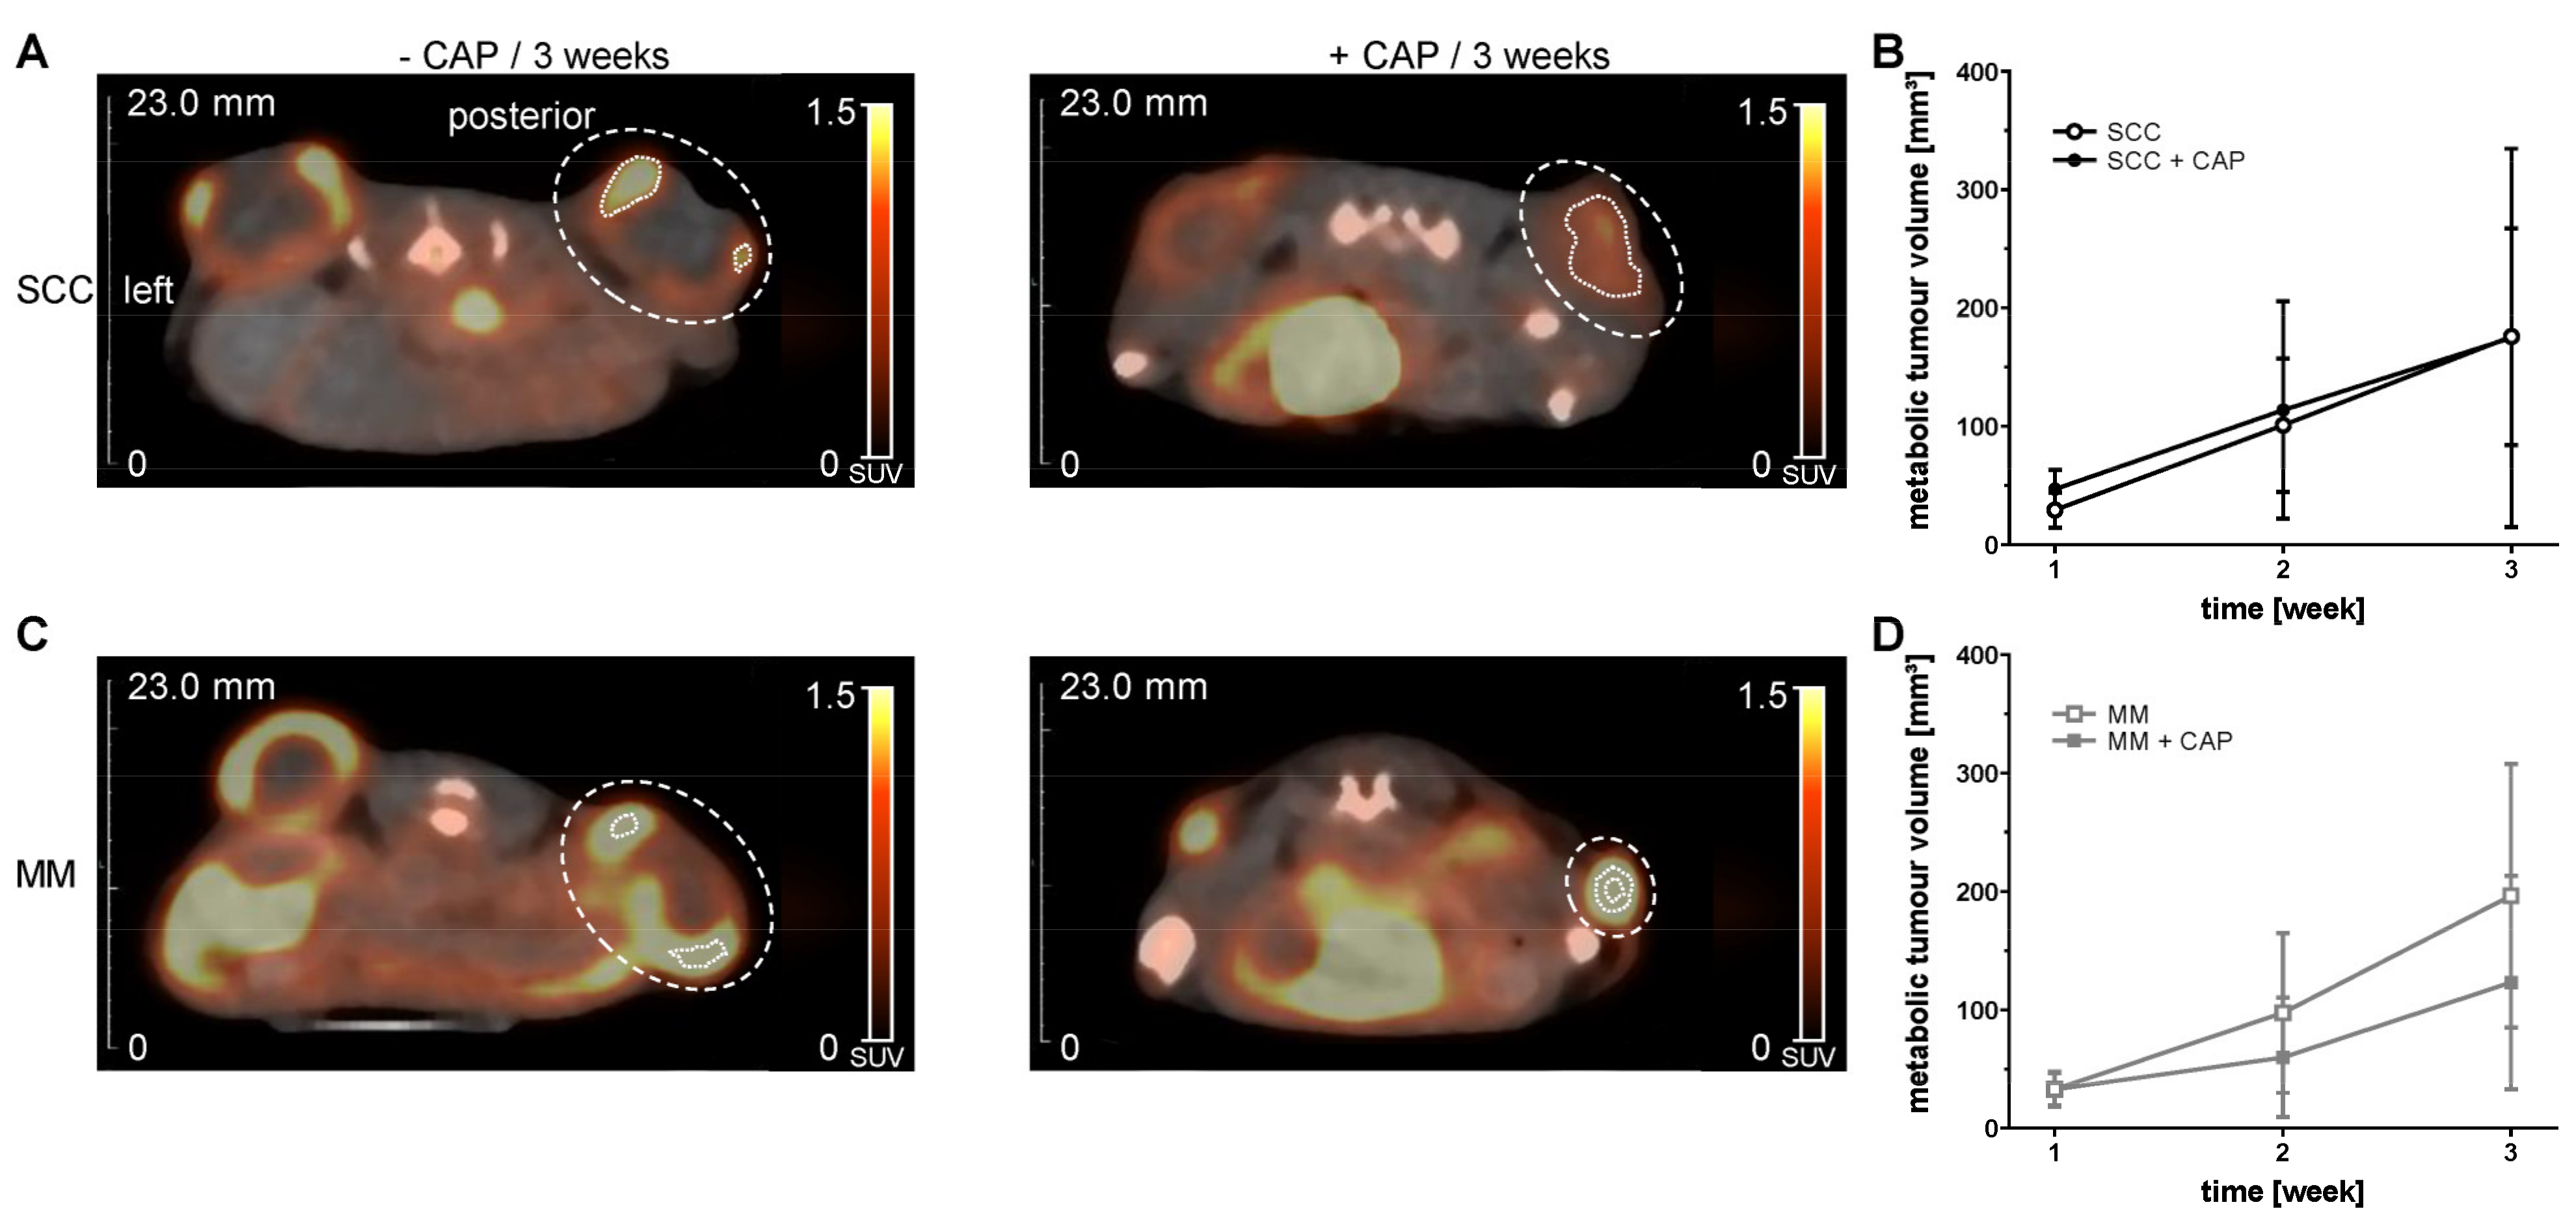

In order to assess the effect of CAP on the MTV of the two tumour entities, we carried out PET/CT examinations using [18F]FDG radiotracer (Figure 3A–D). Three weeks after CAP treatment, no effect on MTV could be determined in SCC (Figure 3B). In contrast, CAP treatment reduced the MTV in MM over time (Figure 3D).

Figure 3.

Representative PET/CT images from [18F]FDG (A,C; summed images, axial slices) and quantitative assessment of metabolic tumour volumes (B,D). NSG mice with two s.c. flank tumours, either squamous cell carcinoma (SCC) or malignant melanoma (MM), were treated with or without cold atmospheric pressure plasma (CAP) over three weeks. CAP treatment started four days after tumour cell injection and was repeated every four days. Data are presented as mean ± SD (n = 6–20 samples per time point); mixed-effects analysis, followed by Bonferroni correction. Large, dotted line mark manually placed volume of interest. Short, dotted line mark right metabolic tumour volume.

In this study, MTV determined by 18[F]FDG PET/CT showed no significant decrease under CAP treatment, although a tendency could be observed in MM. The reduced MTV could be an indication of the therapeutic effect of the CAP treatment, similar to the increase in ADC values after the CAP treatment. It has already been shown in an in vivo study with MM that the treatment response was indicated by an increased ADC value and also a reduced uptake of 18[F]FDG [39]. It cannot be excluded that partial volume effects, or the limited spatial resolution of the PET could have obscured a decrease in MTV after CAP treatment, although we only included the 40% of the hottest voxels in the tumour VOI to reduce partial volume effects. Furthermore, a biased selection of the VOI, due to manual placement, could have occurred. However, fused PET and CT images and visual inspection in all three planes were used for VOI placement to reduce any observer bias.